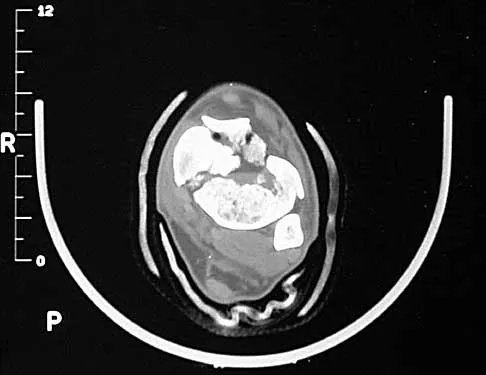

A 14-year-old boy reports pain in the distal thigh. He denies any history of trauma. Examination reveals tenderness and swelling of the distal thigh without effusion. A radiograph and CT scan are shown in Figures 10a and 10b. A biopsy specimen is shown in Figure 10c. Management should consist of

Explanation

Based on these findings, the patient has an aneurysmal bone cyst. Frequently, fluid-fluid levels can be detected on MRI or CT images. The histologic results show a lesion that consists of cavernous spaces filled with blood. The lining of the cavity contains spindle cells, multinucleated giant cells, and reactive bone. Curettage and bone grafting is the preferred treatment method. Without treatment, these lesions can become quite large and destructive. Radiation therapy is not recommended for resectable lesions. Chemotherapy is not required for these benign lesions. Simon MA, Springfield DS, et al: Common Benign Bone Tumors: Surgery for Bone and Soft Tissue Tumors. Philadelphia, PA, Lippincott Raven, 1998, pp 194-200.